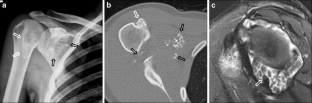

Fig. 1